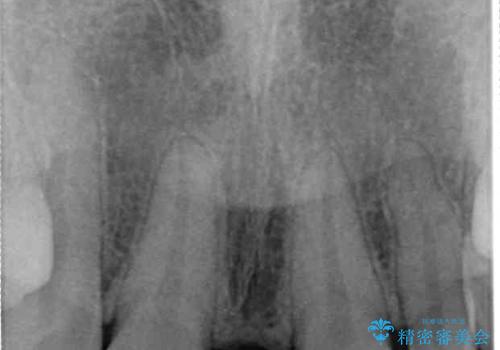

診察の結果、前歯が1本欠損しており、さらに矮小歯(通常よりも小さい歯)が1本存在していました。

欠損による前歯のスペースが大きかったため、事前にワイヤー矯正で前歯の位置を大きく動かし、その後は上下をインビザラインで整えることとしました。

前歯のスペースは、堅い線維の通った歯肉があり、幅も大きかったことから、歯肉切除を行った上でワイヤー矯正により移動を行いました。また、上唇小帯も歯間部付近まで付着していたため、合わせて切除しました。

ワイヤー矯正により、インビザラインよりも早く、歯軸の向きもコントロールしながら移動させることができました。